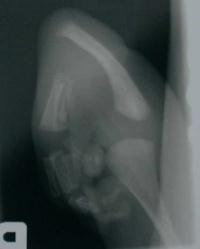

Clinical Example: Radial club hand with complete absence of the radius

This two week old has a high grade radial club hand with a normal opposite extremity. The presentation is unusual for a radial club, as the thumb is relatively normal, with syndactylyl and hypoplasia of the ulnar hand.